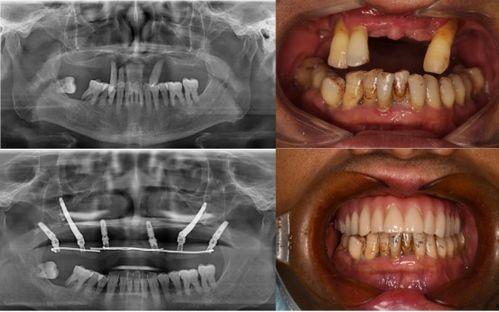

最近佛山那边的种牙事件可是闹得沸沸扬扬的,咱们得好好来聊聊这个话题。你有没有听说,佛山某口腔医院因为种牙问题引发了一场不小的风波?别急,让我带你一探究竟,看看这背后到底隐藏着怎样的秘密。一、事件起因:患者种牙后出现严重问题话...